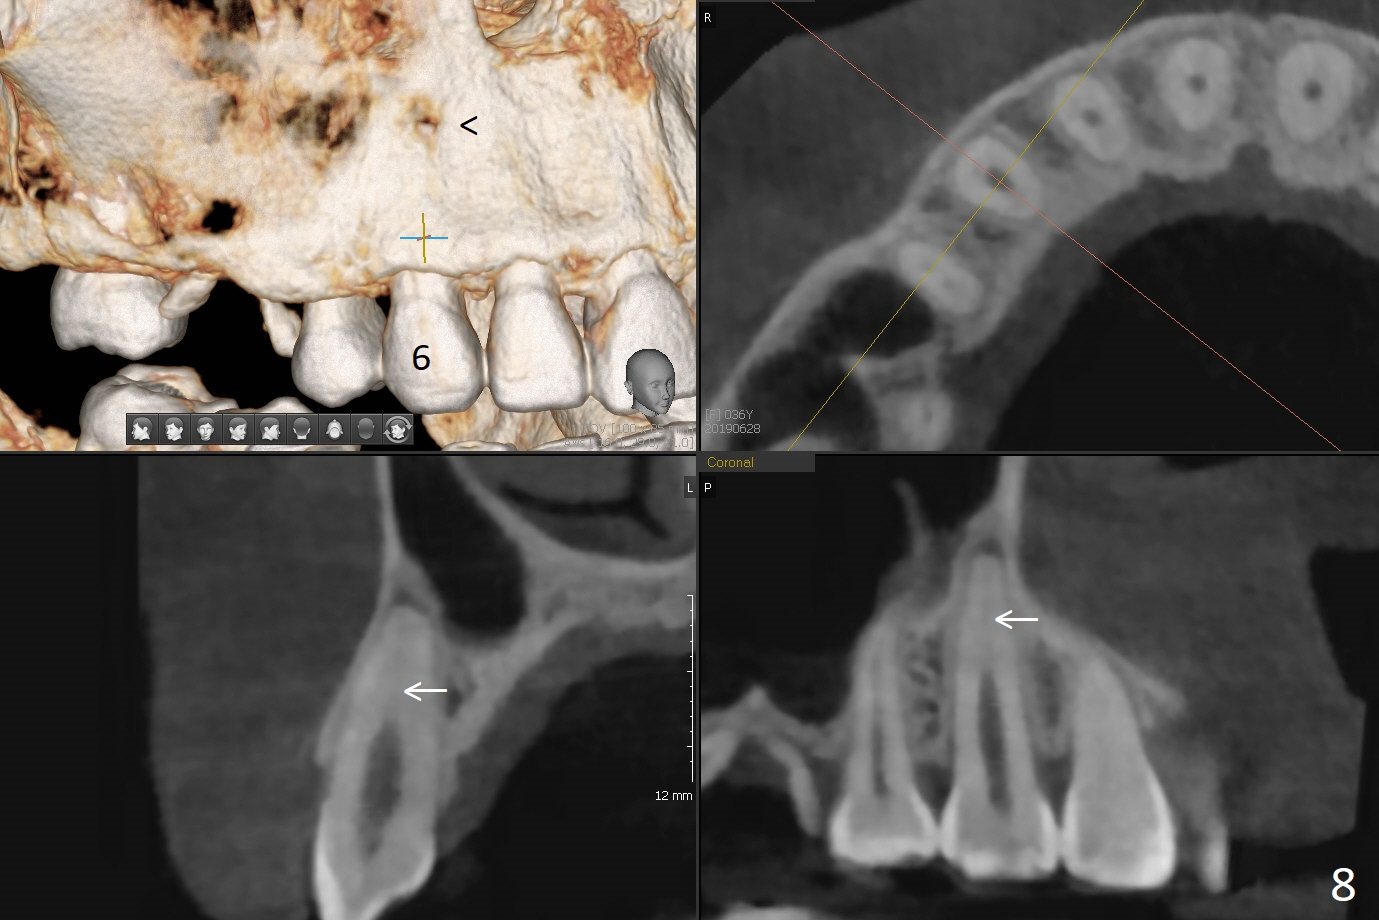

A 36-year-old woman is nervous about dentistry. She will take Valium by herselft before surgery (Fig.1). The tooth #3 has 3 residual roots (Fig.2 (CBCT 3 D occlusal view)). The bone is 2-3 mm thick (Fig.3,4 (sagittal, coronal sections)). A 5x7.3 mm implant will be placed with IS guide (Fig.5 (12 mm offset)). Since IBS implants are able to achieve amazing stability in the thin bone, prepare the shortest 4-5 mm in diameter dummy implants (IS (better surface treatment) and IBS) after sinus lift using UF Guided Sinus Lift Approach Kit (surgery). With intact tooth structure at #14, the bone height is not much (Fig.6), congenital (genetic) in nature. The infection at #31 is more severe (Fig.7). Extraction will be the 2nd in order. Because of limited bone, it is better to do bone graft first. The patient is concerned about the discolored upper right canine, which should be associated with orthodontics 20 years ago (take photos). The apical canal is obliterated (Fig.8,9 arrow) with periapical radiolucency (arrowhead). In fact the bone at #31 is so little that the tooth will be extracted for socket preservation.